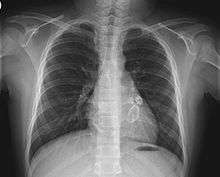

The heart complications are the most important aspect of Kawasaki disease. It is the main cause of heart disease acquired in childhood in the United States and Japan.[23] In developed nations, it appears to have replaced acute rheumatic fever as the most common cause of acquired heart disease in children.[7] Coronary artery aneurysms occur as a sequela of the vasculitis in 20-25% of untreated children.[43] It is first detected at a mean of 10 days of illness and the peak frequency of coronary artery dilation or aneurysms occurs within four weeks of onset.[39] Aneurysms are classified into small (internal diameter of vessel wall <5 mm), medium (diameter ranging from 5–8 mm), and giant (diameter > 8 mm).[23] Saccular and fusiform aneurysms usually develop between 18 and 25 days after the onset of illness.[7]

Even when treated with high-dose IVIG regimens within the first 10 days of illness, 5% of children with Kawasaki disease develop at the least transient coronary artery dilation and 1% develop giant aneurysms.[44][45][46] Death can occur due either to myocardial infarction secondary to blood clot formation in a coronary artery aneurysm or to rupture of a large coronary artery aneurysm. Death is most common two to 12 weeks after the onset of illness.[7]

Many risk factors predicting coronary artery aneurysms have been identified,[13] including persistent fever after IVIG therapy,[47][48] low hemoglobin concentrations, low albumin concentrations, high white-blood-cell count, high band count, high CRP concentrations, male sex, and age less than one year.[49] Coronary artery lesions resulting from Kawasaki disease change dynamically with time.[3] Resolution one to two years after the onset of the disease has been observed in half of vessels with coronary aneurysms.[50][51] Narrowing of the coronary artery, which occurs as a result of the healing process of the vessel wall, often leads to significant obstruction of the blood vessel and lead to the heart not receiving enough blood and oxygen.[50] This can eventually lead to heart muscle tissue death (myocardial infarction).[50]

- Echocardiogram may show subtle coronary artery changes or, later, true aneurysms.

- Angiography was historically used to detect coronary artery aneurysms, and remains the gold standard for their detection, but is rarely used today unless coronary artery aneurysms have already been detected by echocardiography.